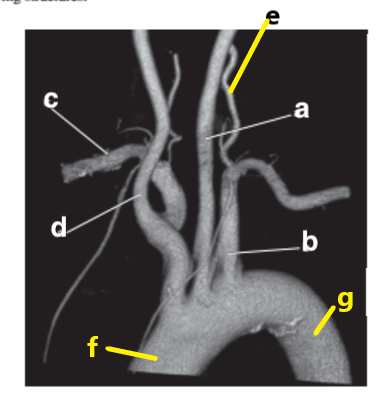

Which letter is the Right vertebral artery ?

f

Which letter is the Left common carotid ?

b

Left vertebral artery

What is letter h ?

Which letter is the left subclavian artery ?

Which letter is the Right common carotid artery ?

d

What is letter a ?

Brachiocephalic trunk

Which letter is the Right coronary artery ?

c

What is letter g ?

Descending aorta

Which letter is the right subclavian artery ?

g

Left anterior descending artery

a

Which letter is the brachiocephalic trunk ?